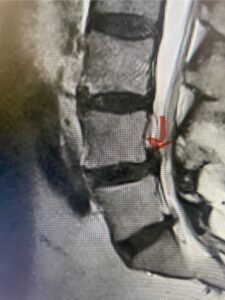

Figs. 1a: Sagittal lumbar T2-weighted MRI demonstrating severe lumbar stenosis with a slight grade 1 at L3-4 and a disc protrusion (red arrow )